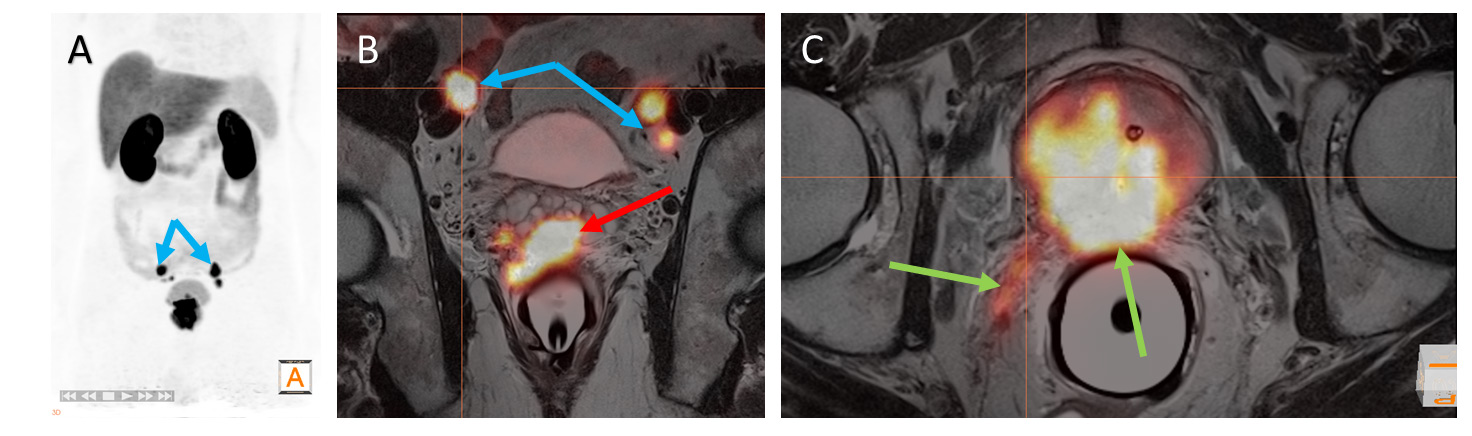

(Vienna, 24. September 2018) Modern medical imaging provides accurate information about the extent (staging) of prostate cancer. PSMA ligand PET/MRI offers a so-called "one-stop-shop" method for accurately staging newly diagnosed prostate cancers, allowing treatment to be adapted accordingly. This is the finding of an interdisciplinary study from MedUni Vienna, which has now been published in the leading journal "Clinical Cancer Research".

Up until now, the primary staging of prostate cancer was based on diagnostic modalities with method-inherent limitations. The interdisciplinary working group led by Markus Hartenbach from the Division of Nuclear Medicine has now demonstrated the outstanding diagnostic value of [68Ga]Ga-PSMA 11 PET/MRI in the primary staging of prostate cancer confirmed by needle biopsy. PSMA ligand PET/MRI not only produced very good results in local and whole-body staging compared to histology but led to a change in the initially planned clinical strategy in nearly one third of patients.

The working group examined 122 patients using PSMA ligand PET/MRI prior to scheduled radical prostatectomy (RP). The primary endpoint was the performance of PSMA ligand PET/MRI in cancer staging compared with staging histology (histological whole-mount sections of the prostate, histology of lymph node dissection and metastatic biopsies). In addition to this, a multidisciplinary team re-evaluated the initial therapeutic approach in order to assess the impact of PSMA ligand PET/MRI on clinical management.

In the final analysis, PSMA ligand PET/MRI correctly identified the cancer in 119 out of 122 patients (97.5%). Moreover, PSMA ligand PET/MRI changed the clinical strategy in 28.7% of patients, either in favour of systemic treatment/radiotherapy, because of a locally advanced stage and/or remote metastases, or so-called active surveillance, because the primary tumour was not visible or only minimally visible on the scan.